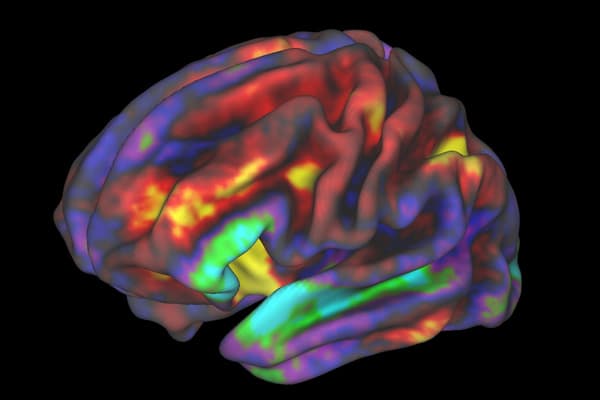

fMRI scans, which measure brain activity through blood flow changes, provide a much more dynamic view than an MRI or other scans, but because of this detailed imaging, they produce a large amount of data that is difficult to interpret. The Georgia State team built an AI modeling program that can interpret the immense amount of fMRI brain scan data. Through its data interpretation, the program was able to discover novel patterns linked with mental health conditions that could help future medical professionals prevent and more easily treat these disorders.

The team also was able to data mine existing fMRI scans in individuals without a known disorder to improve the model’s performance on more specific datasets, and new patterns emerged for each of the mental health conditions. The scientists began with a dataset with more than 10,000 scans, allowing the AI program to understand fMRI imaging and brain function, before using it on more than 1,200 scans of those with Alzheimer’s, autism, and schizophrenia.

Results of the study showed the AI program was able to not only identify early signs of the disorders, but also pinpoint the time at which it was most likely to occur. The study holds impressive implications for identifying markers in patients and predicting risk early enough to offer better and more effective treatments. The study also provides numerous new avenues for research in the same vein that focus on early predictors of other disorders.